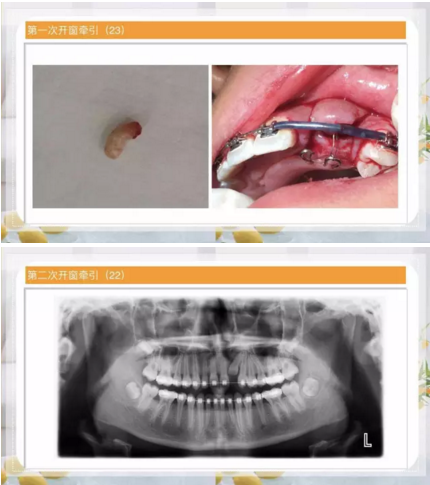

阻生齒外科聯(lián)合正畸治療

24.png

25.png

26.png